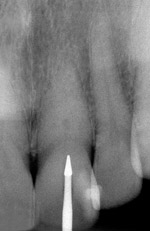

Fig. 23 Radiograph of deeper endo-exploration with the latch grip version of the conical carbide bur. Position confirmed as accurate.

Figure 23

Fig. 24 Shortly after Figure 23 radiograph was taken, the ideal angle of intersection of the residual pulp nicely directs the file into the calcified pulp chamber

Figure 24